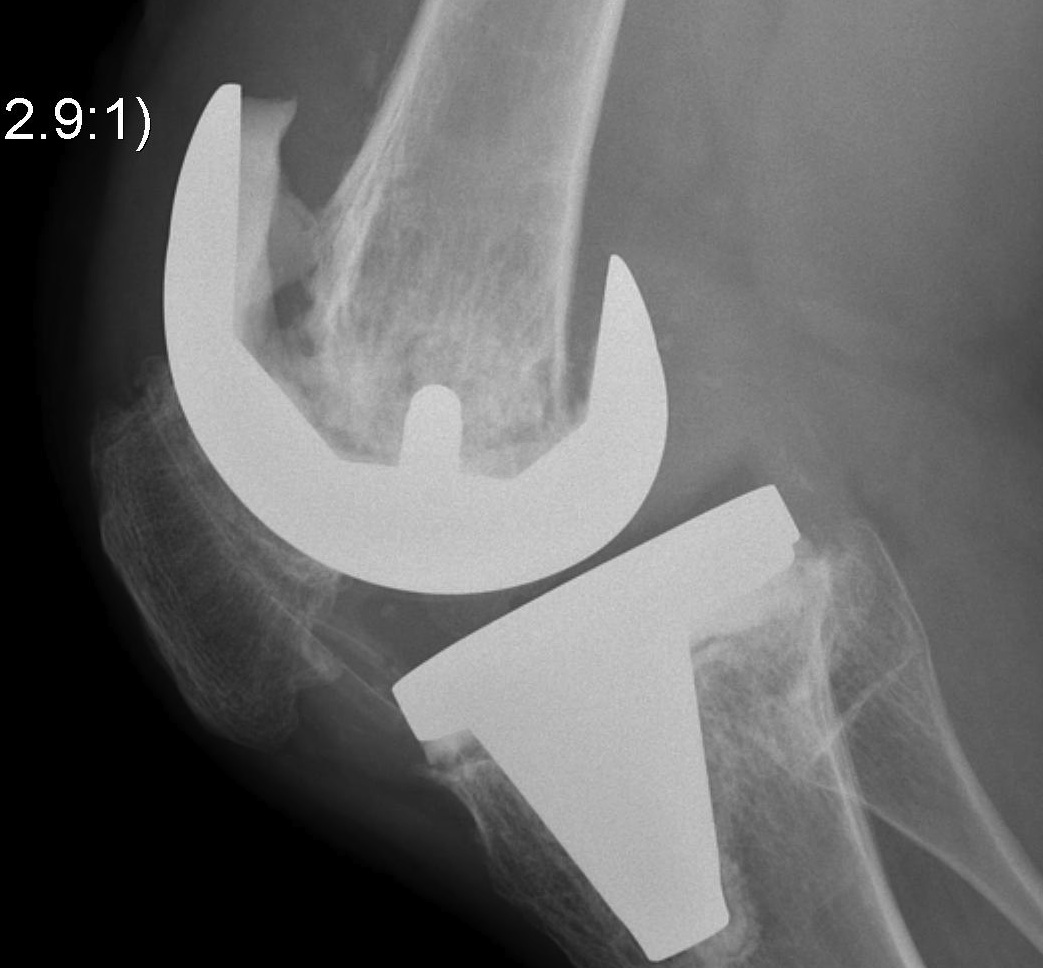

B. Tantalum cones metaphyseal filling / Trabecular metal

Meneghini et al JBJS Am 2009

- tantalum porous tibial implant in 15 pateints followed average 3 years

- AORI type 3 and type 2B

- knee society score average 85

- all had evidence osteointegration, no loosening

Howard et al JBJS Am 2011

- femoral tantalum components in 24 knees followed for averag 3 years

- knee society score average 81

- all well fixed with no complications